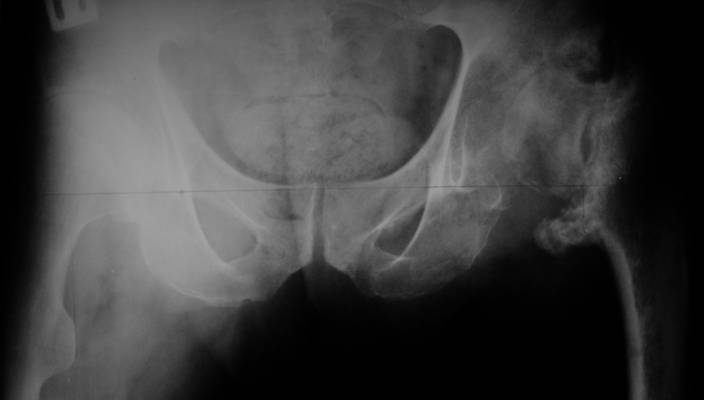

Re: несросшаяся шейка бедра

До травмы проблем с ногой не было. Укорочения, болей и т.п. не отмечал. Сегодня перемерял укорочение - меньше 7 см намерять не

По уровню малых вертелов (с учетом рентгеновского увеличения) получается 5 см. Клинически ногу низвести путем тракции невозможно. Из движений - сгибание до 40*, остальные движения "символические".